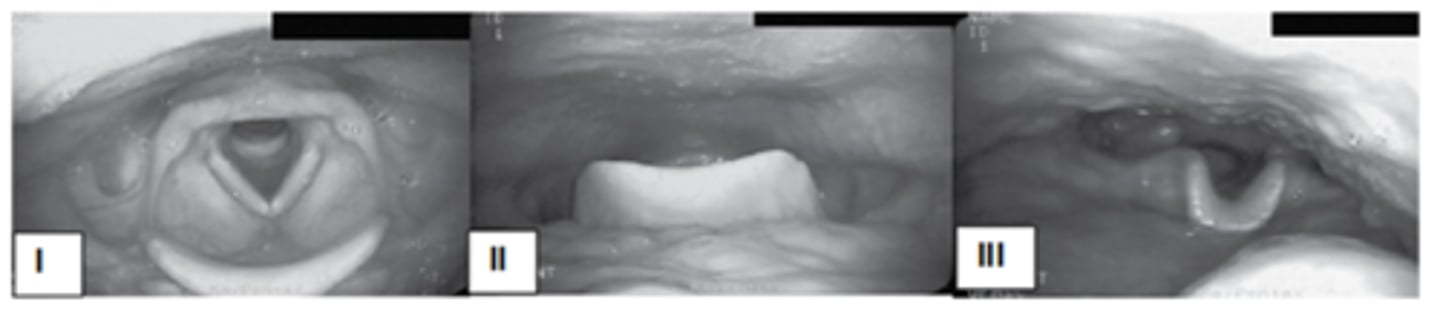

The pictures show the endoscopic view of three different head postures on the oropharyngeal structure. Use these pictures to answer the following two questions.

A dysphagia patient with unilateral pharyngeal deficit may benefit from ___________________________.

III

Which posture widens the oropharynx?

I